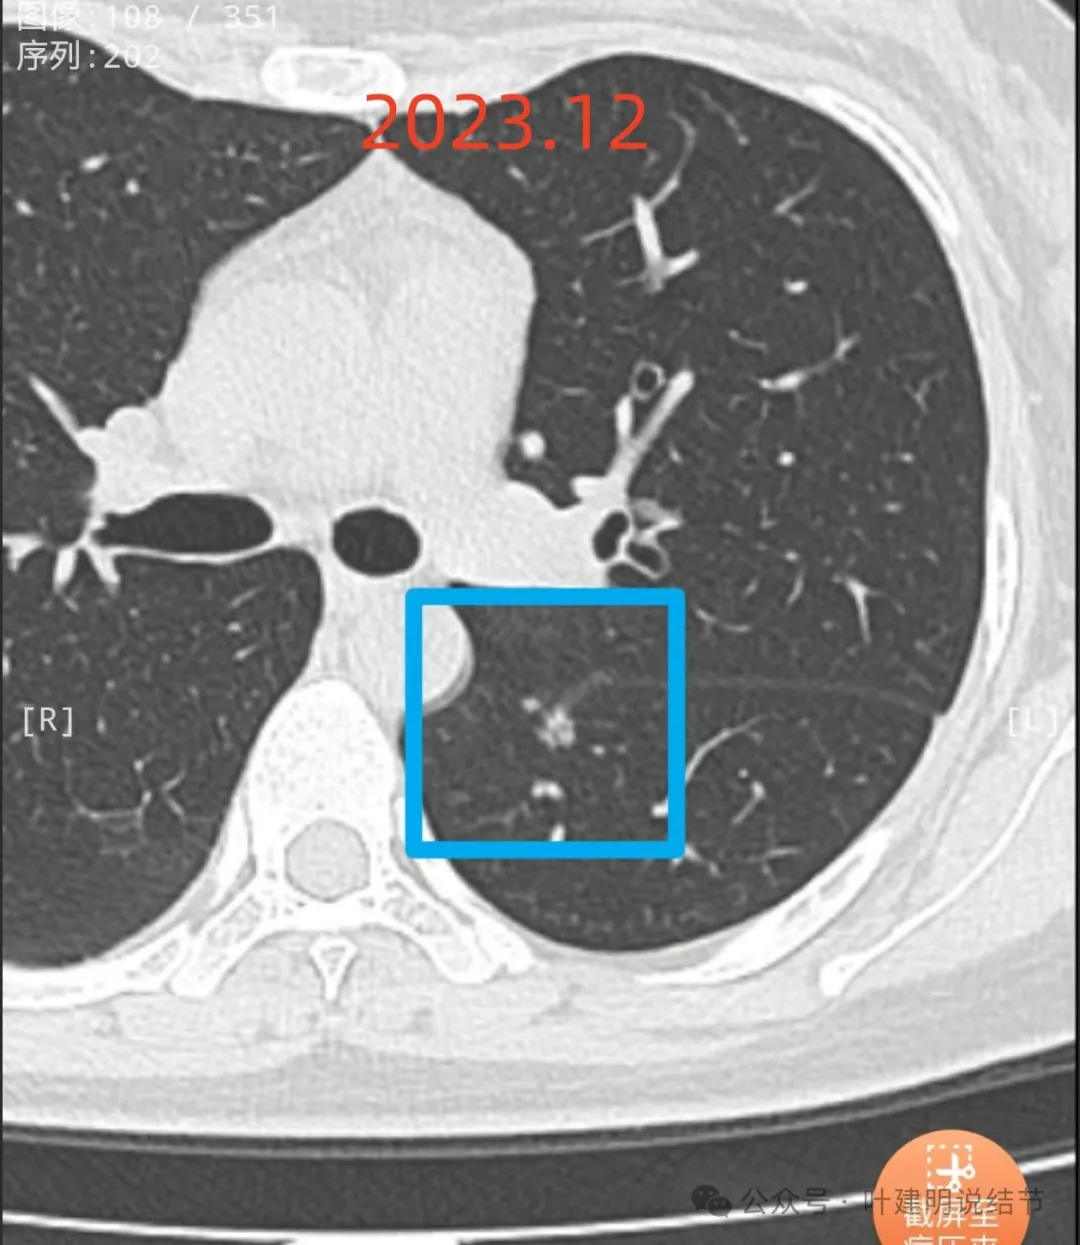

先看不同时间段最明显层面的影像:

2023年12月再复查,进展倒是并不明显,但边缘似有小棘突状,叶间裂似乎有点牵拉。